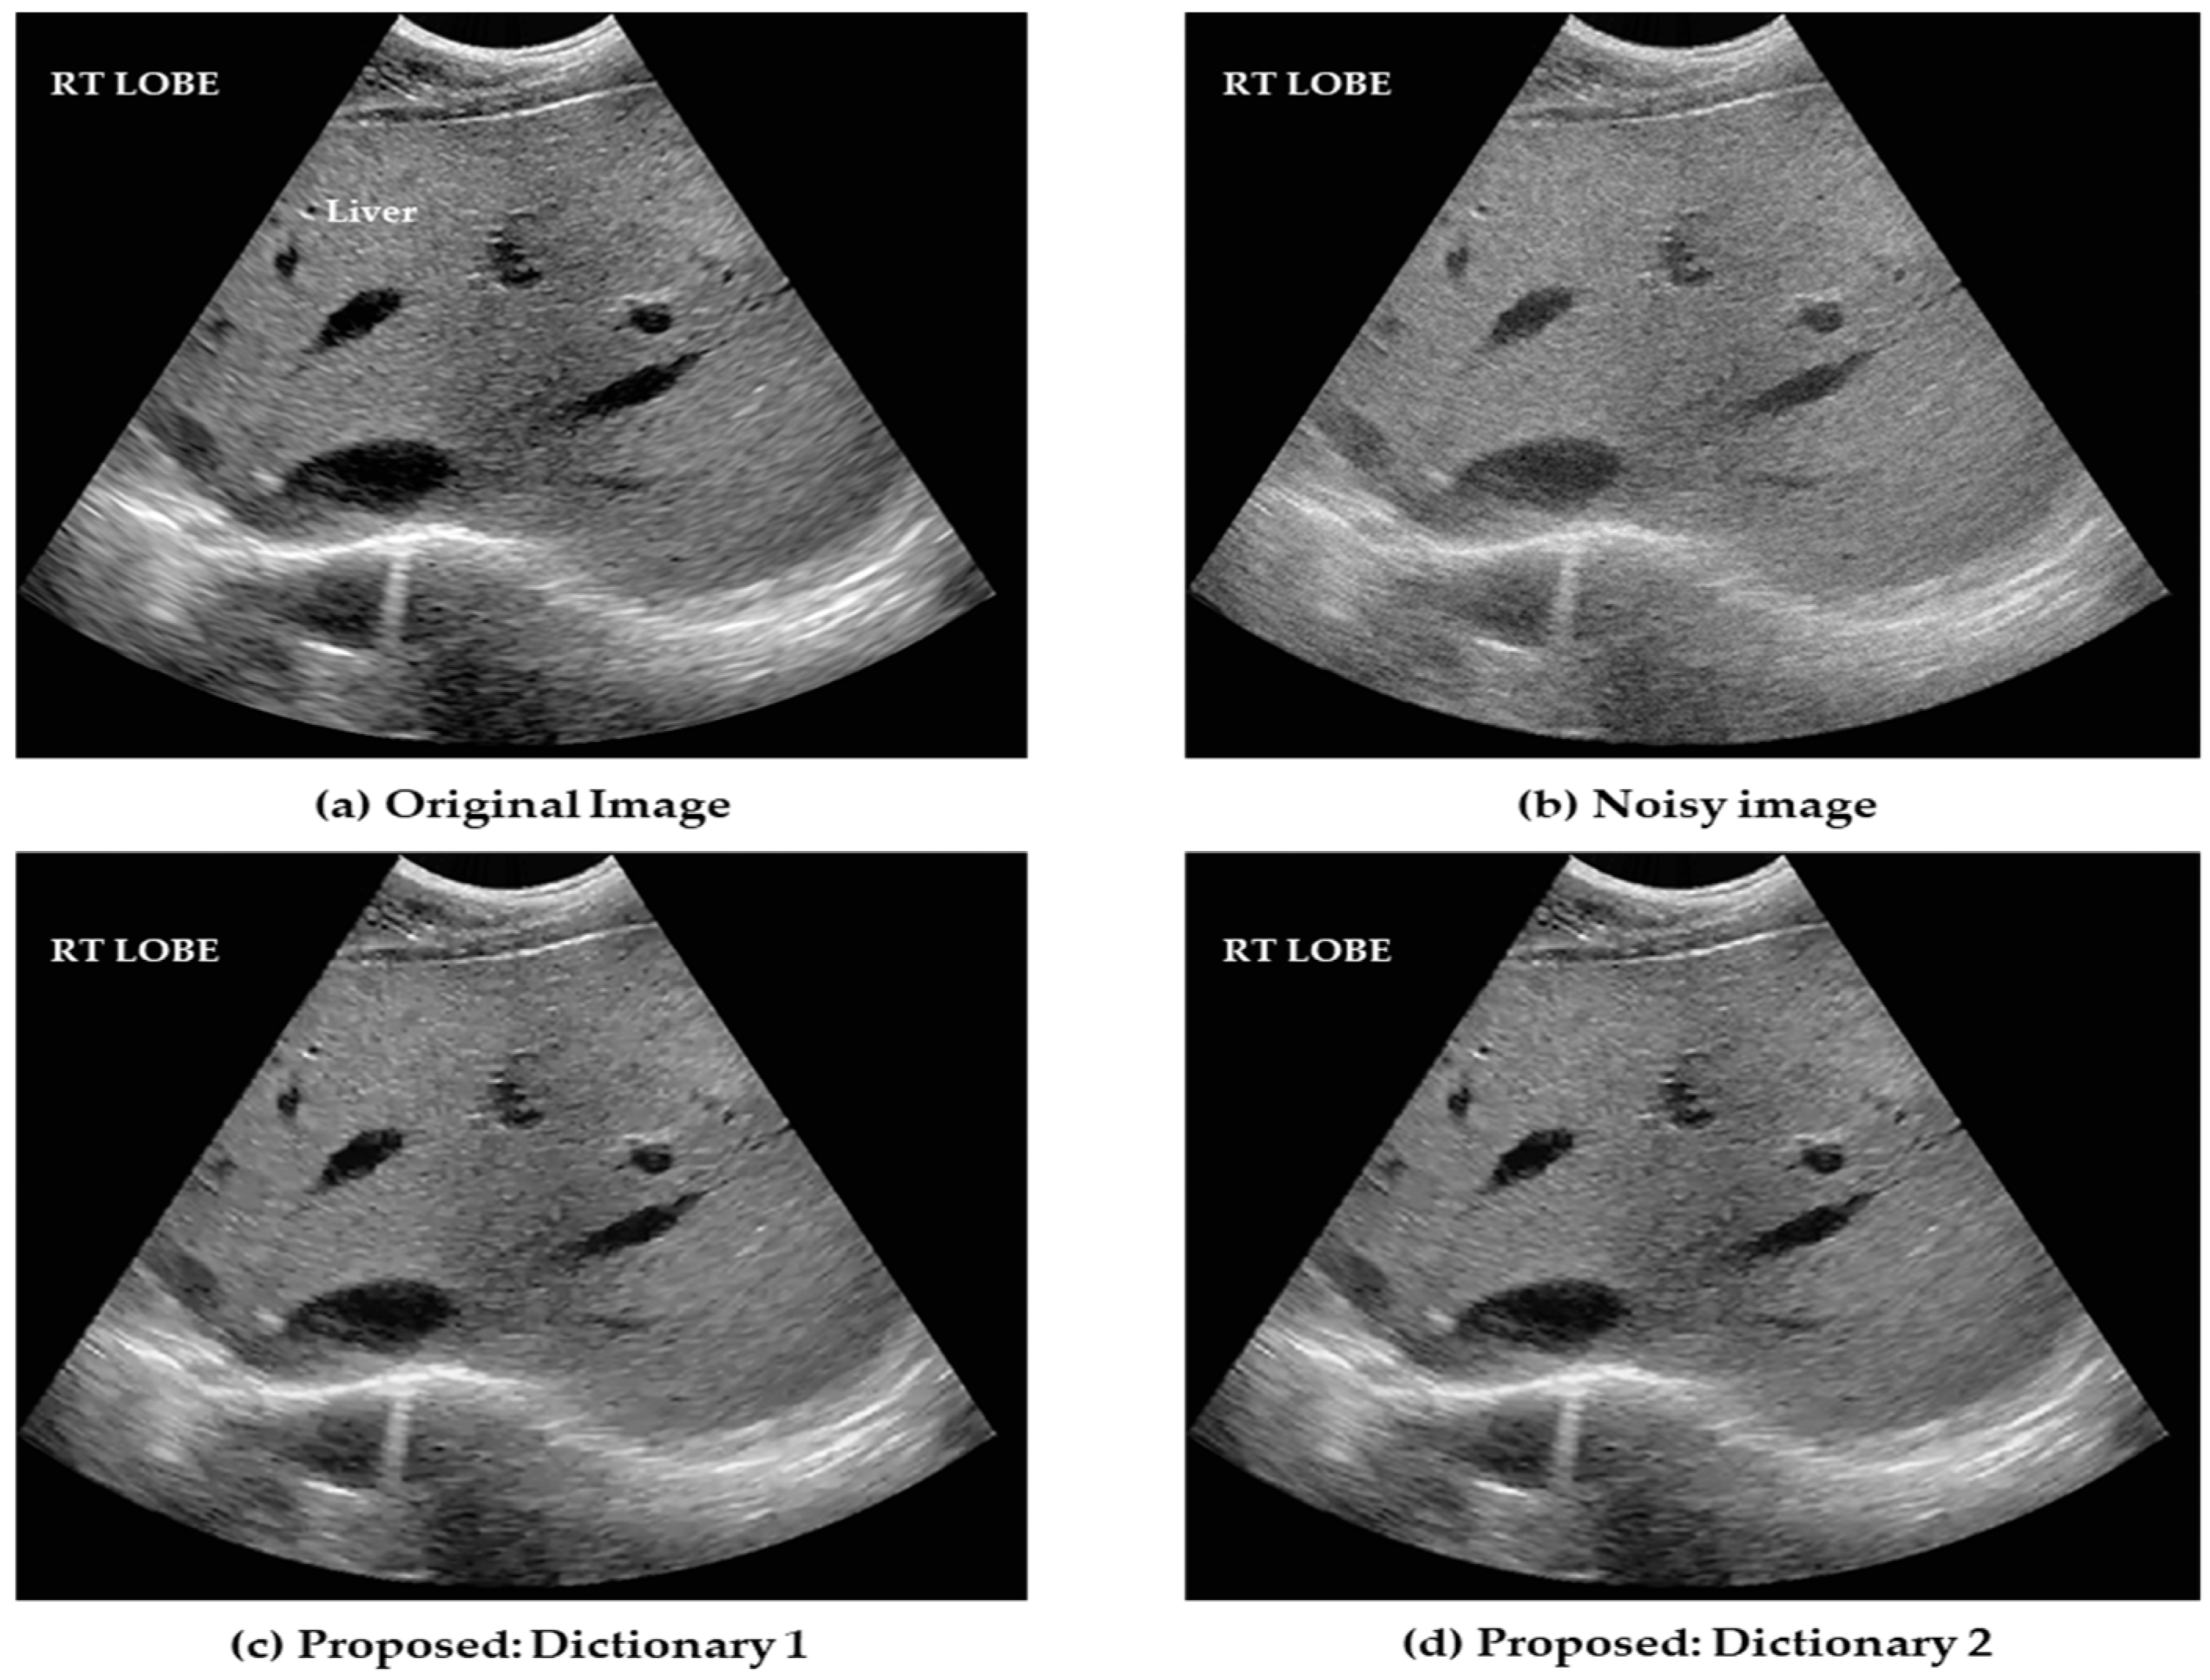

4.2. Clinical Liver Ultrasound Images

| Proposed: Dictionary 1 | 36.862 | 0.953 |

| Proposed: Dictionary 2 | 37.044 | 0.967 |